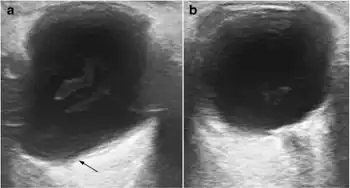

a) Shows the lengthened anteroposterior axis of right eye, with a pear-shaped posterior pole sacculation known as a staphyloma b) compare with the normal left globe